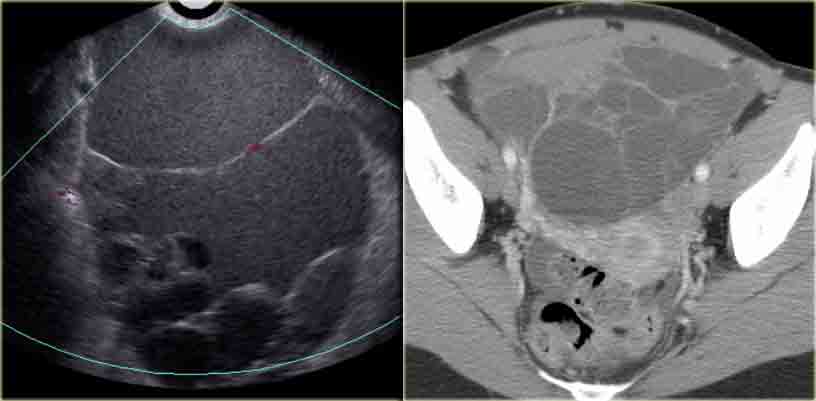

The transvaginal ultrasound images show a small complex ovarian cyst with wall vascularity on power Doppler analysis.

The characteristic circular Doppler appearance is called the 'ring of fire'.

Note, there is good through-transmission and no internal vascularity, consistent with a, partially involuted, corpus luteum cyst.

Corpus luteum cyst Corpus luteum cyst

Another case with the typical the 'ring of fire' on ultrasound.

At pathologic examination the collapsed bloody cyst can be clearly seen.

Corpus luteum cyst at MRI: an axial T2-weighted image demonstrating an involuting corpus luteum cyst (arrow).

This is a normal finding.

The right ovary is also normal.